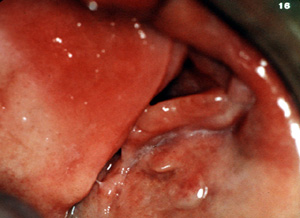

Aquí son

dos épulis, bilaterales, en los vestíbulos del maxilar. Es una

apariencia típica. Son lobulados y

muestran áreas focales aumentadas de vascularidad. En la porción

central de cada masa hay una ranura ó una invaginación

que corre en una dirección anterior-posterior. La pestaña de la

dentadura postiza encajará en estas ranuras.